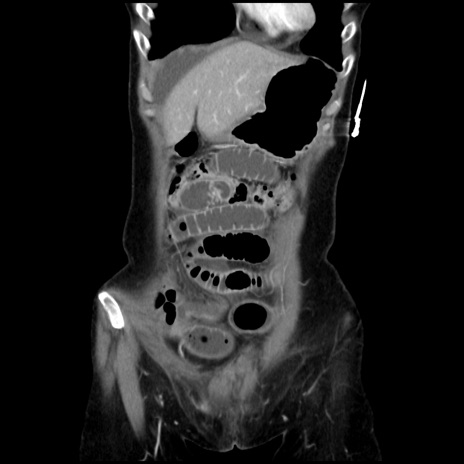

症例32(冠状断像)

【症例】40歳代 女性

【主訴】上腹部痛、嘔気・嘔吐

【現病歴】約9時間前頃から急に上腹部痛、嘔気、嘔吐が出現。改善しないため救急要請。

【既往歴】子宮頚癌(広汎子宮全摘術、放射線療法)、腸閉塞

【身体所見】腹部:平坦、軟、腸雑音亢進、上腹部を中心に腹部全体に圧痛あり。

【データ】WBC 8400、CRP 0.03